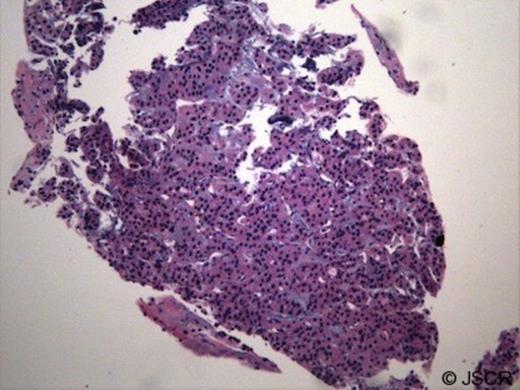

The thyroid gland was noted to be homogeneously enlarged and (a random?) fine needle aspiration was performed by ultrasound guidance. CT-guided biopsy of the mediastinal mass showed nests of epithelioid cells with clear cytoplasm and organoid pattern. The tumour stained positive for vimentin. Staining for thyroglobulin was not performed. Biopsy of the mediastinal mass was labeled paraganglioma [figure 4] and of the thyroid, a benign goiter. Thyroid function testing was normal.

Microscopic examination of the mediastinal mass biopsy (H and E stain): revealed tumour cells with benign appearance and histologic features consistent with paraganglioma